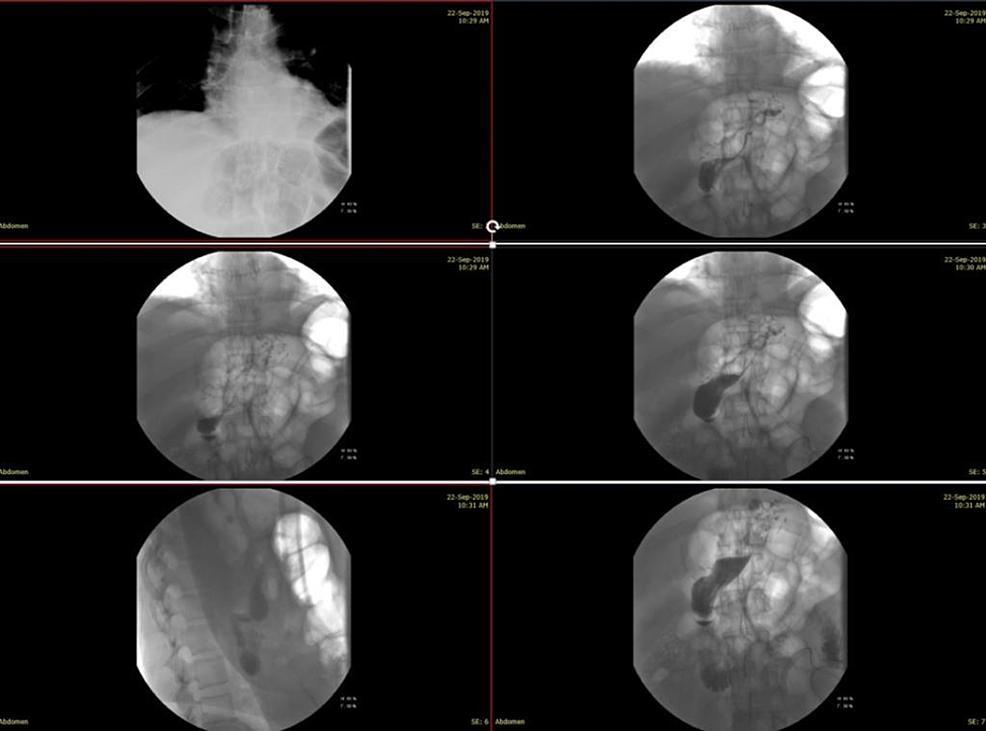

From www.researchgate.net

Upper GI series revealing gastric leak. Download Scientific Diagram Post Sleeve Gastrectomy Leak A missed or delayed diagnosis can. The presentation of leak after laparoscopic sleeve gastrectomy (lsg) is variable. This study aims to share outcomes of our management algorithm of post lsg leak, including the rate of resolution, complications, admission. Leaks after sleeve gastrectomy remain a deadly complication significantly affecting outcomes and medical costs. • our update for endoscopic treatment of leak. Post Sleeve Gastrectomy Leak.